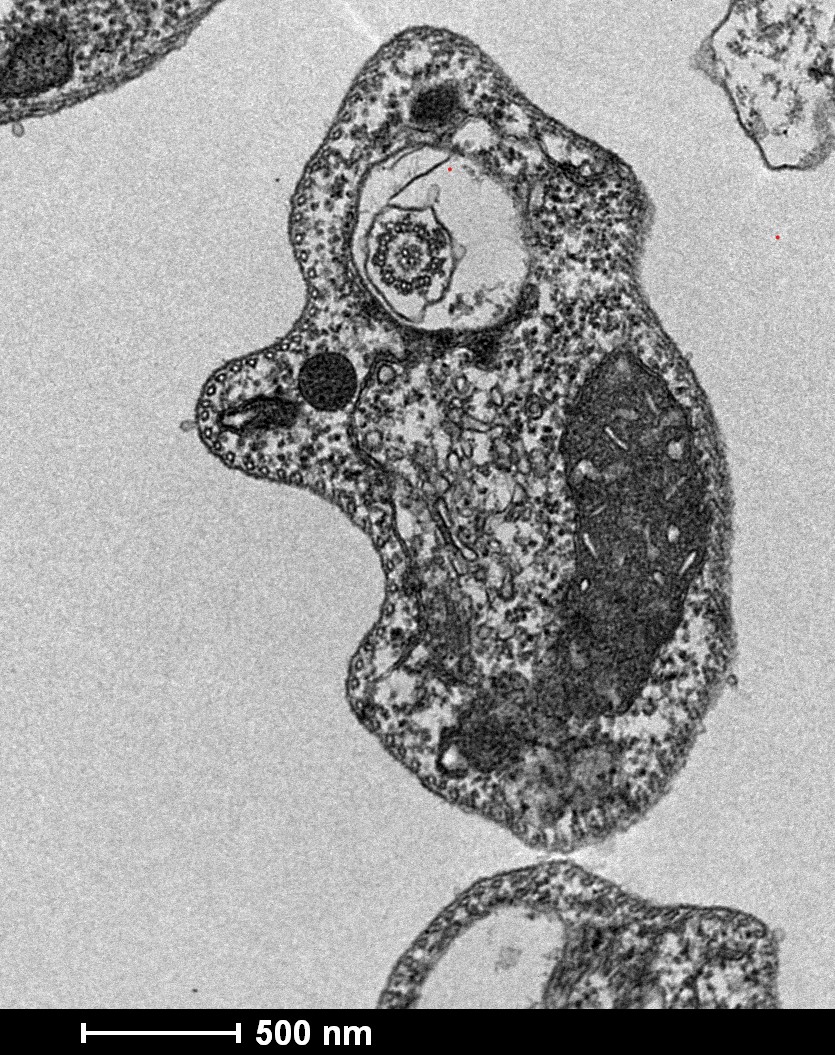

Imagem de microscopia eletrônica de transmissão de promastigota de Leishmania amazonensis axênicas tratadas com Complemento Humano.

Equipamento: Microscópio Eletrônico de Transmissão – Tecnai G2-12 Spirit Biotwin 120kV

Imagem cedida por Laura Valeria Rios Barros e Thiago de Castro Gomes – Departamento de Parasitologia, ICB, UFMG